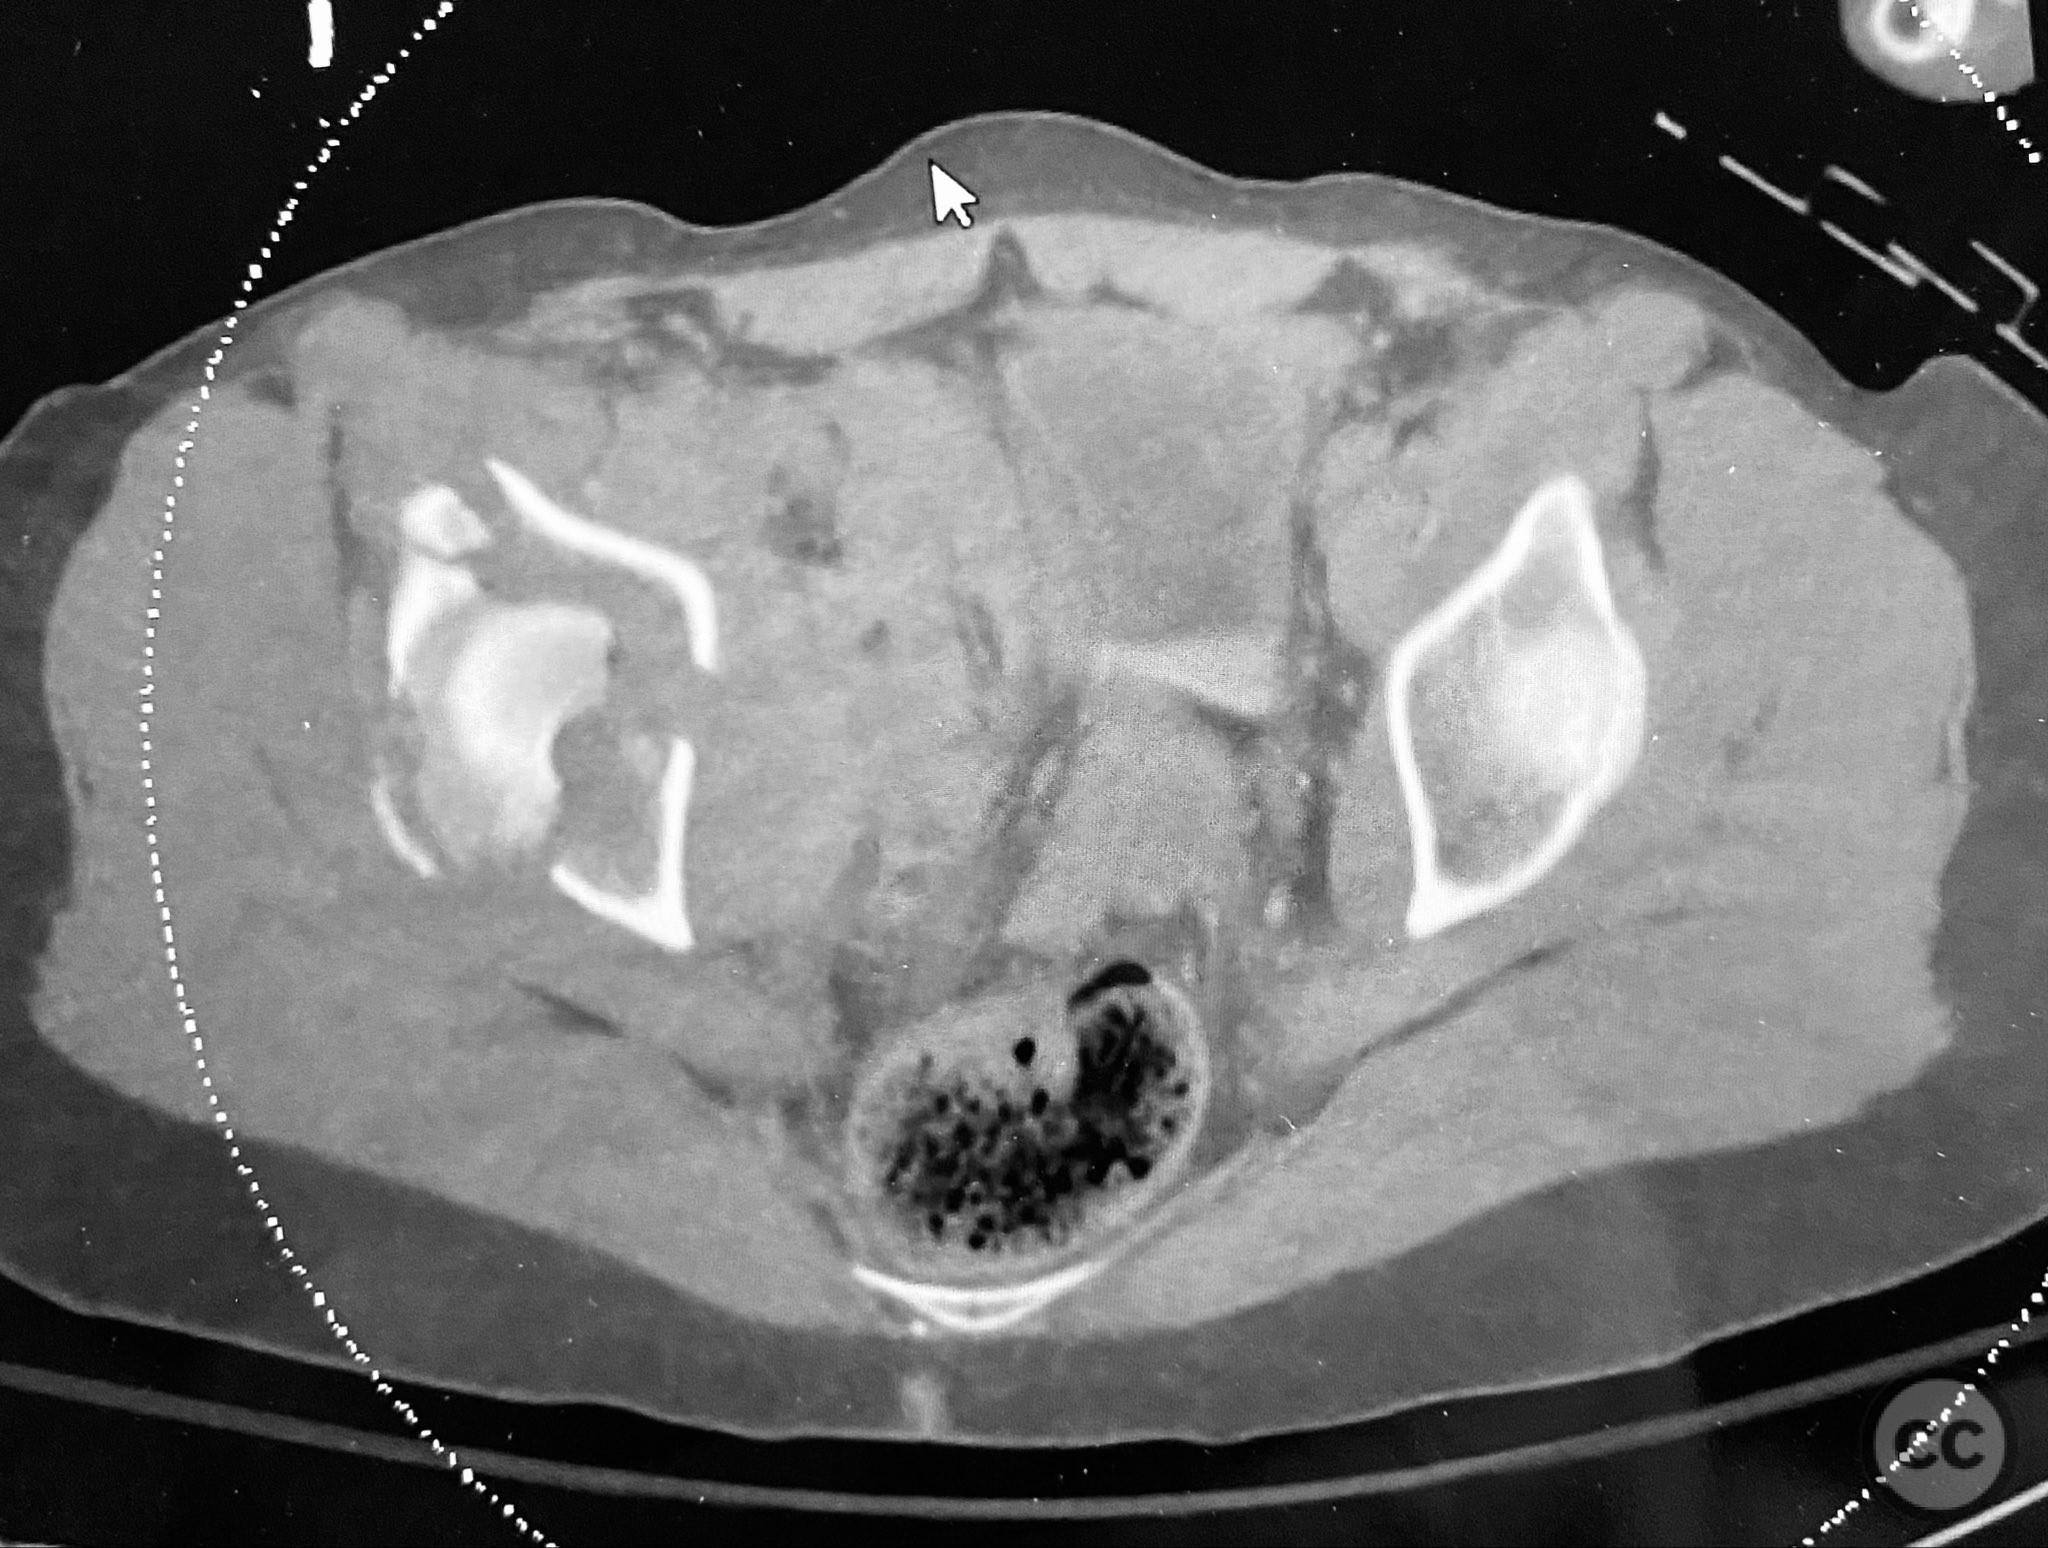

Clinical and radiological findings:  The patient sustained a complex both column acetabular fracture, AO/OTA 62C1, characterized by several large columnar fragments, an independent anterior inferior iliac spine (AIIS) fragment, a notable dome fragment predominantly attached to the posterior wall (PW) fragment, and a distinct parasymphyseal injury zone. Initial application of a pelvic binder resulted in increased displacement of the fracture fragments. Preoperative imaging, including surface renderings and multiplanar CT, demonstrated the independent AIIS fragment, detailed cortical surfaces, and the orientation of fracture planes. The majority of the acetabular dome was associated with the PW fragment, a critical detail for surgical planning and reduction.

The anterior column fragment was reduced first under direct visualization and held with a 6-hole plate and lag screw. The 12-hole intrapelvic plate was then contoured and applied along the pelvic brim to reinforce the reduction. The posterior column and posterior wall fragments, including the dome component, were stabilized with lag screws placed through safe osseous corridors under fluoroscopic guidance. The independent AIIS fragment was addressed during the exposure and incorporated into the reduction construct. The parasymphyseal injury zone was inspected for stability following fixation. Postoperative CT confirmed anatomical reduction and stable fixation of all fragments.